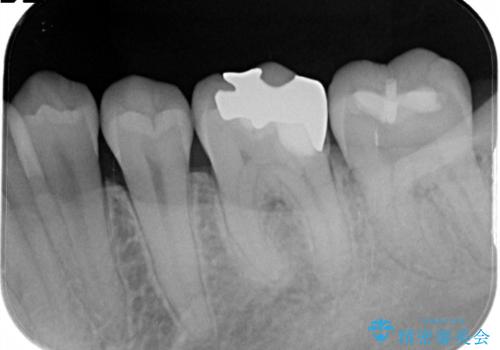

- 定期検診にて金属の下に虫歯を認めた患者様です。

拡大鏡を用い丁寧に虫歯を除去した後セラミックインレーにて修復治療を行っております。

修復物の適合は虫歯の再発リスクに影響する大切な要素です。